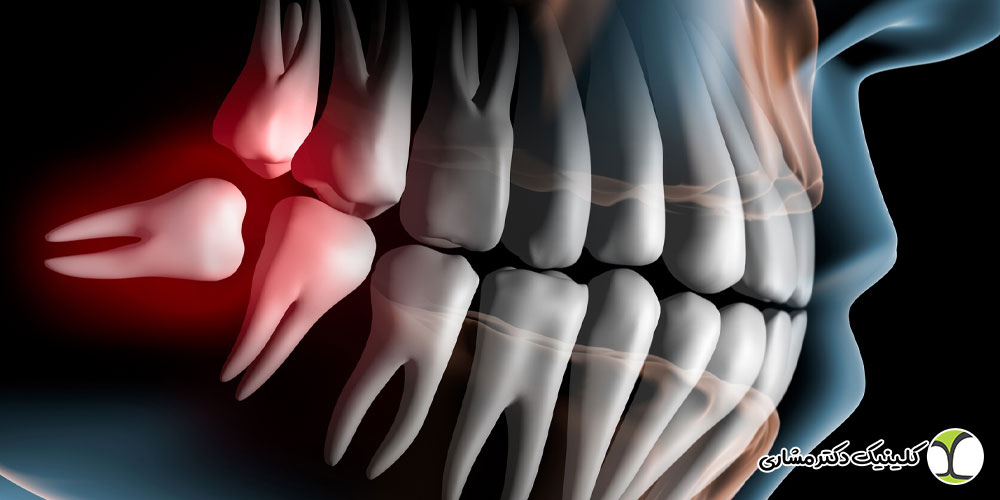

دندان عقل معمولاً آخرین دندانی است که در دهان رویش پیدا میکند و به دلیل کمبود فضا در فک، در بسیاری از افراد بهصورت نهفته یا نیمهنهفته باقی میماند. در برخی موارد، موقعیت رویش و فرم ریشههای دندان عقل بهگونهای است که ریشه دندان با عصب فک تحتانی (Inferior Alveolar Nerve) تماس نزدیک دارد یا حتی مستقیماً روی آن قرار میگیرد.

به این وضعیت، اصطلاحاً دندان عقل درگیر با عصب یا دندان عقل روی عصب گفته میشود. شدت این درگیری میتواند متفاوت باشد؛ از نزدیکی ساده تا احاطه کامل عصب توسط ریشه دندان.

چرا برخی دندانهای عقل روی عصب قرار میگیرند؟

در بسیاری از موارد، اگر دندان عقل در زمان مناسب بررسی شود، میتوان قبل از ایجاد درگیری شدید با عصب، تصمیم درمانی صحیح گرفت. اما در حالت کلی دلایل اصلی شامل موارد زیر است:

- کمبود فضای فک برای رویش کامل دندان عقل

- شکل نامناسب یا انحنای شدید ریشهها

- رویش افقی یا مایل دندان

- ژنتیک و فرم استخوان فک

- تأخیر در تشخیص و بررسی در سنین پایین